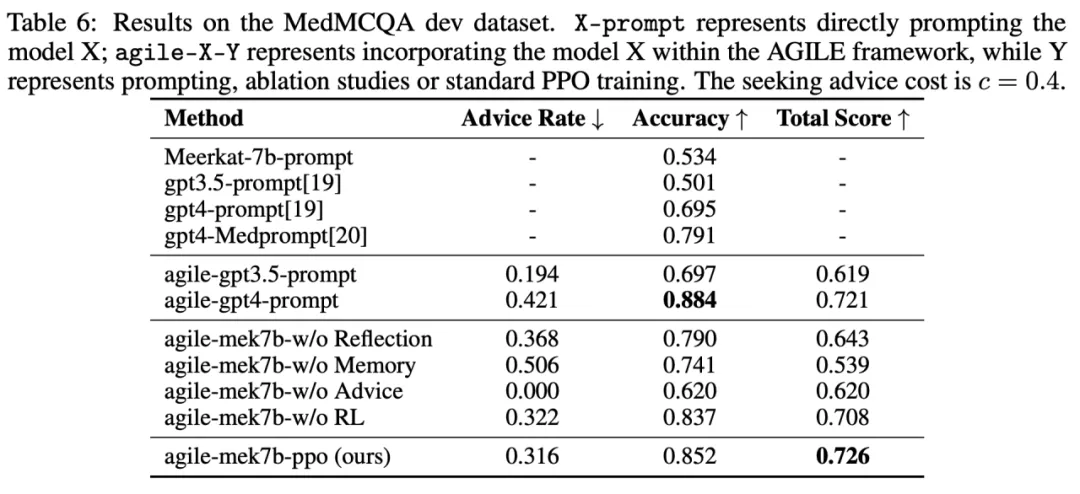

MedMCQA

MedMCQA 是一个多项选择的问答数据集,其问题来自医学院入学考试。在 MedMCQA 任务上,基于 Meerkat-7b 训练的 AGILE Agent(agile-mek7b-ppo)表现优于 GPT-4 Agent。准确率达到了 85.2%,超过了之前的 SOTA 方法 ——GPT 4-MedPrompt 的 79.1%。消融实验结果进一步验证了记忆、咨询人类建议、反思和 RL 训练的重要性。